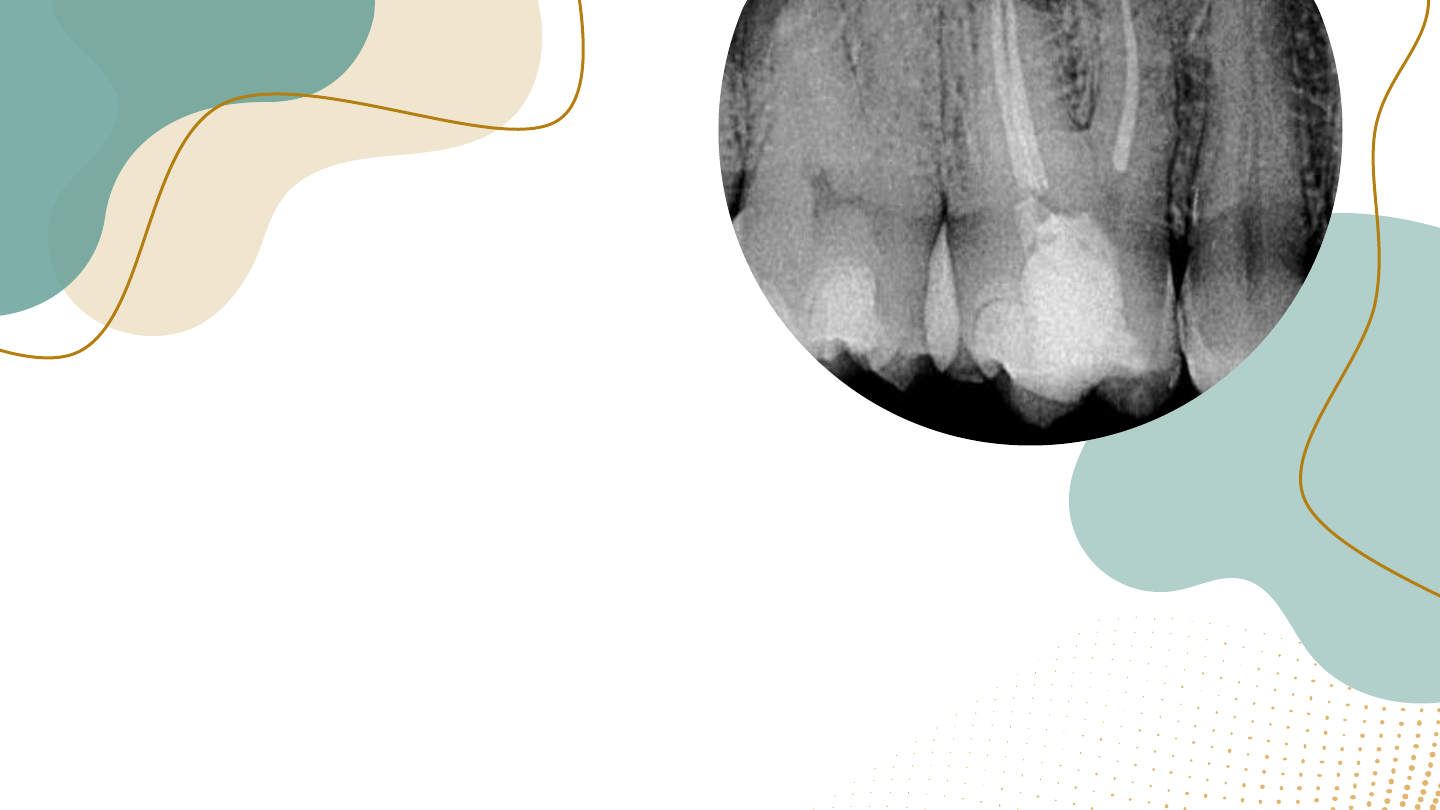

<p>Alterações pulpares</p><p>e perapicais</p><p>Componentes: Débora Torres, Larissa Myrela, Maria Vitória, Lílian</p><p>Suiane, Leandro Vasconcelos, Antônio Ismael, Yury Ismael</p><p>Definição</p><p>➢ Alterações pulpares referem-se a problemas na</p><p>polpa dental, como inflamação ou necrose.</p><p>➢ Alterações periapicais envolvem as áreas ao</p><p>redor da raiz do dente, geralmente relacionadas</p><p>a infecções.</p><p>1. A polpa dentária é um tecido conjuntivo mole que reside no interior da coroa e da raiz dos dentes. É composta por</p><p>células, vasos sanguíneos, nervos e tecido conjuntivo. A polpa tem funções vitais, como a formação da dentina, a</p><p>nutrição do dente e a sensibilidade ao frio, calor e pressão. Sua saúde é fundamental para a vitalidade do dente.</p><p>Anatomia e Fisiologia da Polpa Dentária</p><p>Camadas da Polpa</p><p>A polpa é composta por várias camadas, cada</p><p>uma com sua função especifica a polpa coronal a</p><p>polpa radicular e o complexo odontoblástico.</p><p>Polpa Coronal: Encontradana coroa do dente,</p><p>abriga a maioria das células da polpa e vasos</p><p>sanguíneos</p><p>Polpa Radicular: Localizada dentro da raiz do</p><p>dente, contém menos células e mais tecido</p><p>conjuntivo.</p><p>Complexo Odontoblástico: Carmada periférizada</p><p>polpa, composta pelos odontoblastos, células</p><p>responsáveis pela formação da dentina</p><p>Vascularização e Inervação</p><p>A polpa é ricamente vascularizada, o que garante o</p><p>suprimento sanguíneo necessário para suas</p><p>funções. A inervação é igualmente importante,</p><p>transmitindo sensações de dore temperatura an</p><p>cérebro.</p><p>Artérias: Fornecem sangue oxigenado à polpa,</p><p>através da entrada no ápice da raiz do dente</p><p>Velas: Drenam o sangue da polpa, através da</p><p>mesma entrada no ápice.</p><p>Nervos: Transmitem sinais sensoriais ao cérebro.</p><p>proporcionando a sensibilidade dentária.</p><p>1. A inflamação da polpa, conhecida como pulpíte, pode manifestar-se de diversas formas, dependendo</p><p>da gravidade e da causa. Os sintomas podem variar de dor leve e passageira a dor intensa, constante e</p><p>incapacitante. Em casos de infecção, a dor pode ser pulsátil e irradiar para outras áreas da face, além</p><p>de causar inchaço e sensibilidade à pressão</p><p>2. Dor espontânea:</p><p>3. Dor provocada:</p><p>4. Sensibilidade dentária:</p><p>Sintomas de Inflamação e Infecção Pulpar</p><p>1. O tratamento de canal, ou endodontia, é um procedimento que visa tratar a polpa infectada ou necrosada,</p><p>removendo a polpa do canal radicular e o preenchimento do canal com um material biocompatível. O objetivo é</p><p>eliminar a infecção, prevenir a propagação da infecção para os tecidos periapicais e restaurar a função do</p><p>dente.</p><p>Procedimentos de Tratamento de Canal</p><p>Causas comuns de alteracões Pulpares e Periapicais</p><p>01</p><p>Cáries</p><p>Dentárias</p><p>A cárie dentária é a causa mais comum de</p><p>alterações pulpares e periapicais. A</p><p>destruição do esmalte e da dentina por</p><p>bactérias permite que a cárie penetre na</p><p>polpa, causando inflamação e dor.</p><p>02</p><p>Traumatismo</p><p>Dentário</p><p>Um golpe forte no dente pode causar danos</p><p>à polpa, levando a alterações pulpares e</p><p>periapicais. Fraturas e luxações dentárias</p><p>também podem resultar em inflamação e</p><p>infecção.</p><p>03</p><p>Procedimentos</p><p>Dentários</p><p>Procedimentos dentários, como obturações,</p><p>tratamentos de canal e extrações, podem, em</p><p>alguns casos, causar alterações pulpares e</p><p>periapicais, principalmente se não forem</p><p>realizados com técnica adequada ou se houver</p><p>infecção pré-existente.</p><p>04</p><p>Doenças</p><p>Periodontal</p><p>A doença periodontal (gengivite e</p><p>periodontite) pode levar à inflamação</p><p>e infecção do tecido que sustenta o</p><p>dente, afetando a polpa e os tecidos</p><p>periapicais.</p><p>Causas comuns de alterações Pulpares e Perapicais</p><p>Alterações</p><p>Pulpares:</p><p>01</p><p>Pulpite Reversível</p><p>Caracterizada por dor passageira e</p><p>leve, geralmente causada por</p><p>estímulos térmicos ou químicos. A</p><p>polpa ainda está saudável, mas</p><p>inflamada. O tratamento visa eliminar a</p><p>causa da irritação e restaurar o dente.</p><p>Pulpite Irreversível</p><p>A dor é intensa e persistente, podendo</p><p>irradiar para outras áreas da face. A polpa</p><p>está severamente inflamada e</p><p>necrosando. O tratamento geralmente</p><p>envolve tratamento de canal para remover</p><p>a polpa infectada e proteger o dente.</p><p>A polpa está morta e necrosada. O dente</p><p>pode apresentar coloração escura e dor. A</p><p>remoção da polpa morta e o tratamento de</p><p>canal são essenciais para evitar</p><p>complicações.</p><p>Necrose Pulpar</p><p>Entendendo a Polpa do Dente</p><p>Alterações</p><p>Periapicais</p><p>Periodontite Apical</p><p>Infecção na ponta da</p><p>raiz, geralmente</p><p>causada por polpa</p><p>infeccionada. O tecido</p><p>ao redor da raiz inflama</p><p>e incha, podendo</p><p>causar dor,</p><p>sensibilidade e pus.</p><p>Abcesso Periapical</p><p>Acúmulo de pus na ponta</p><p>da raiz, causado por</p><p>infecção. A dor é intensa</p><p>e latejante, podendo</p><p>irradiar para outras áreas</p><p>da face. O tratamento</p><p>geralmente envolve</p><p>drenagem do abscesso e</p><p>tratamento de canal.</p><p>Granuloma perapical</p><p>Massa de tecido inflamatório</p><p>na ponta da raiz, geralmente</p><p>em resposta a uma infecção.</p><p>Pode ser assintomático ou</p><p>causar dor leve e sensibilidade.</p><p>O tratamento geralmente</p><p>envolve tratamento de canal</p><p>para eliminar a infecção.</p><p>O Que Acontece ao Redor da Raiz</p><p>Comparando</p><p>Alterações</p><p>Pulpares e</p><p>Periapicais</p><p>Diagnóstico de Alterações Pulpares e Periapicais:</p><p>Identificando o Problema</p><p>Tratamento de Alterações Pulpares e</p><p>Periapicais: Restaurando a Saúde Bucal</p><p>Tratamento de Canal</p><p>Procedimento para remover a polpa infectada e selar o canal radicular, evitando a propagação da infecção.</p><p>É indicado para pulpite irreversível, necrose pulpar e infecções periapicais.</p><p>Drenagem de Abscesso</p><p>Procedimento para drenar o pus acumulado em um abscesso periapical, aliviando a dor e a inflamação.</p><p>É feito através de uma pequena incisão na gengiva, seguida de limpeza e drenagem.</p><p>Cirurgia Periapical</p><p>Procedimento para remover tecidos infectados ou cistos na ponta da raiz, quando o tratamento de</p><p>canal não é suficiente. Pode ser necessário para tratar granulomas, cistos e infecções complexas.</p><p>Antibióticos</p><p>Prescritos para tratar a infecção, especialmente em casos de abscesso periapical ou periodontite apical.</p><p>A escolha do antibiótico depende da extensão da infecção e dos sintomas do paciente.</p><p>Prevenção de Alterações</p><p>Pulpares e Periapicais:</p><p>Cuidados Essenciais</p><p>A Importância do Acompanhamento</p><p>Profissional: Cuidando da Sua Saúde Bucal</p><p>O acompanhamento profissional regular é crucial para a manutenção da saúde</p><p>bucal e a prevenção de alterações pulpares e periapicais. O dentista é o</p><p>profissional habilitado para diagnosticar e tratar essas condições, além de orientar</p><p>sobre os cuidados preventivos. Não hesite em procurar um dentista caso você</p><p>esteja sentindo dor, sensibilidade ou outros sintomas bucais. A detecção precoce</p><p>de alterações pulpares e periapicais aumenta as chances de tratamento eficaz e</p><p>preservação da saúde do seu sorriso.</p><p>Obrigado</p><p>Slide 1: Alterações pulpares e perapicais</p><p>Slide 2: Definição</p><p>Slide 3: Anatomia e Fisiologia da Polpa Dentária</p><p>Slide 4: Sintomas de Inflamação e Infecção Pulpar</p><p>Slide 5: Procedimentos de Tratamento de Canal</p><p>Slide 6: Causas comuns de alteracões Pulpares e Periapicais</p><p>Slide 7: 03</p><p>Slide 8: Alterações Pulpares:</p><p>Slide 9</p><p>Slide 10: Alterações Periapicais</p><p>Slide 11: O Que Acontece ao Redor da Raiz</p><p>Slide 12: Comparando Alterações Pulpares e Periapicais</p><p>Slide 13</p><p>Slide 14: Diagnóstico de Alterações Pulpares e Periapicais: Identificando o Problema</p><p>Slide 15: Tratamento de Alterações Pulpares e Periapicais: Restaurando a Saúde Bucal</p><p>Slide 16: Prevenção de Alterações Pulpares e Periapicais: Cuidados Essenciais</p><p>Slide 17</p><p>Slide 18: A Importância do Acompanhamento Profissional: Cuidando da Sua Saúde Bucal</p><p>Slide 19: Obrigado</p><p>Slide 20</p>